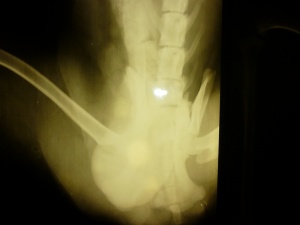

Возили сегодня Филю в ЦВК. Сделали новые снимки. Прогноз неутешительный. В результате травмы задет спинной мозг. Чувствительность задних конечностей практически равна нулю.Очень хочется верить что все таки он сможет хотя бы на трех лапах ходить. Сегодня по приезду домой он умудрился выпрыгнуть с заднего сиденья машины и очень быстро карабкаться через дорогу. До слез пробрало!!! Буду бороться дальше за его здоровье. По прежнему для этого нужны средства.